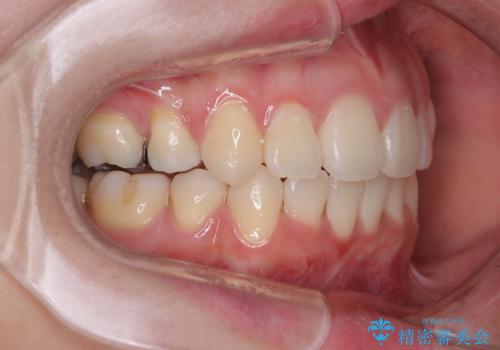

- 下の前歯のデコボコと、口元の突出感を改善したいと来院された患者様です。

上下左右の第一小臼歯を抜歯して、目立ちにくいワイヤー装置で矯正を行いました。

上下の保定用マウスピースの他に、デコボコの強かった下顎前歯にはワイヤーで保定をしています。